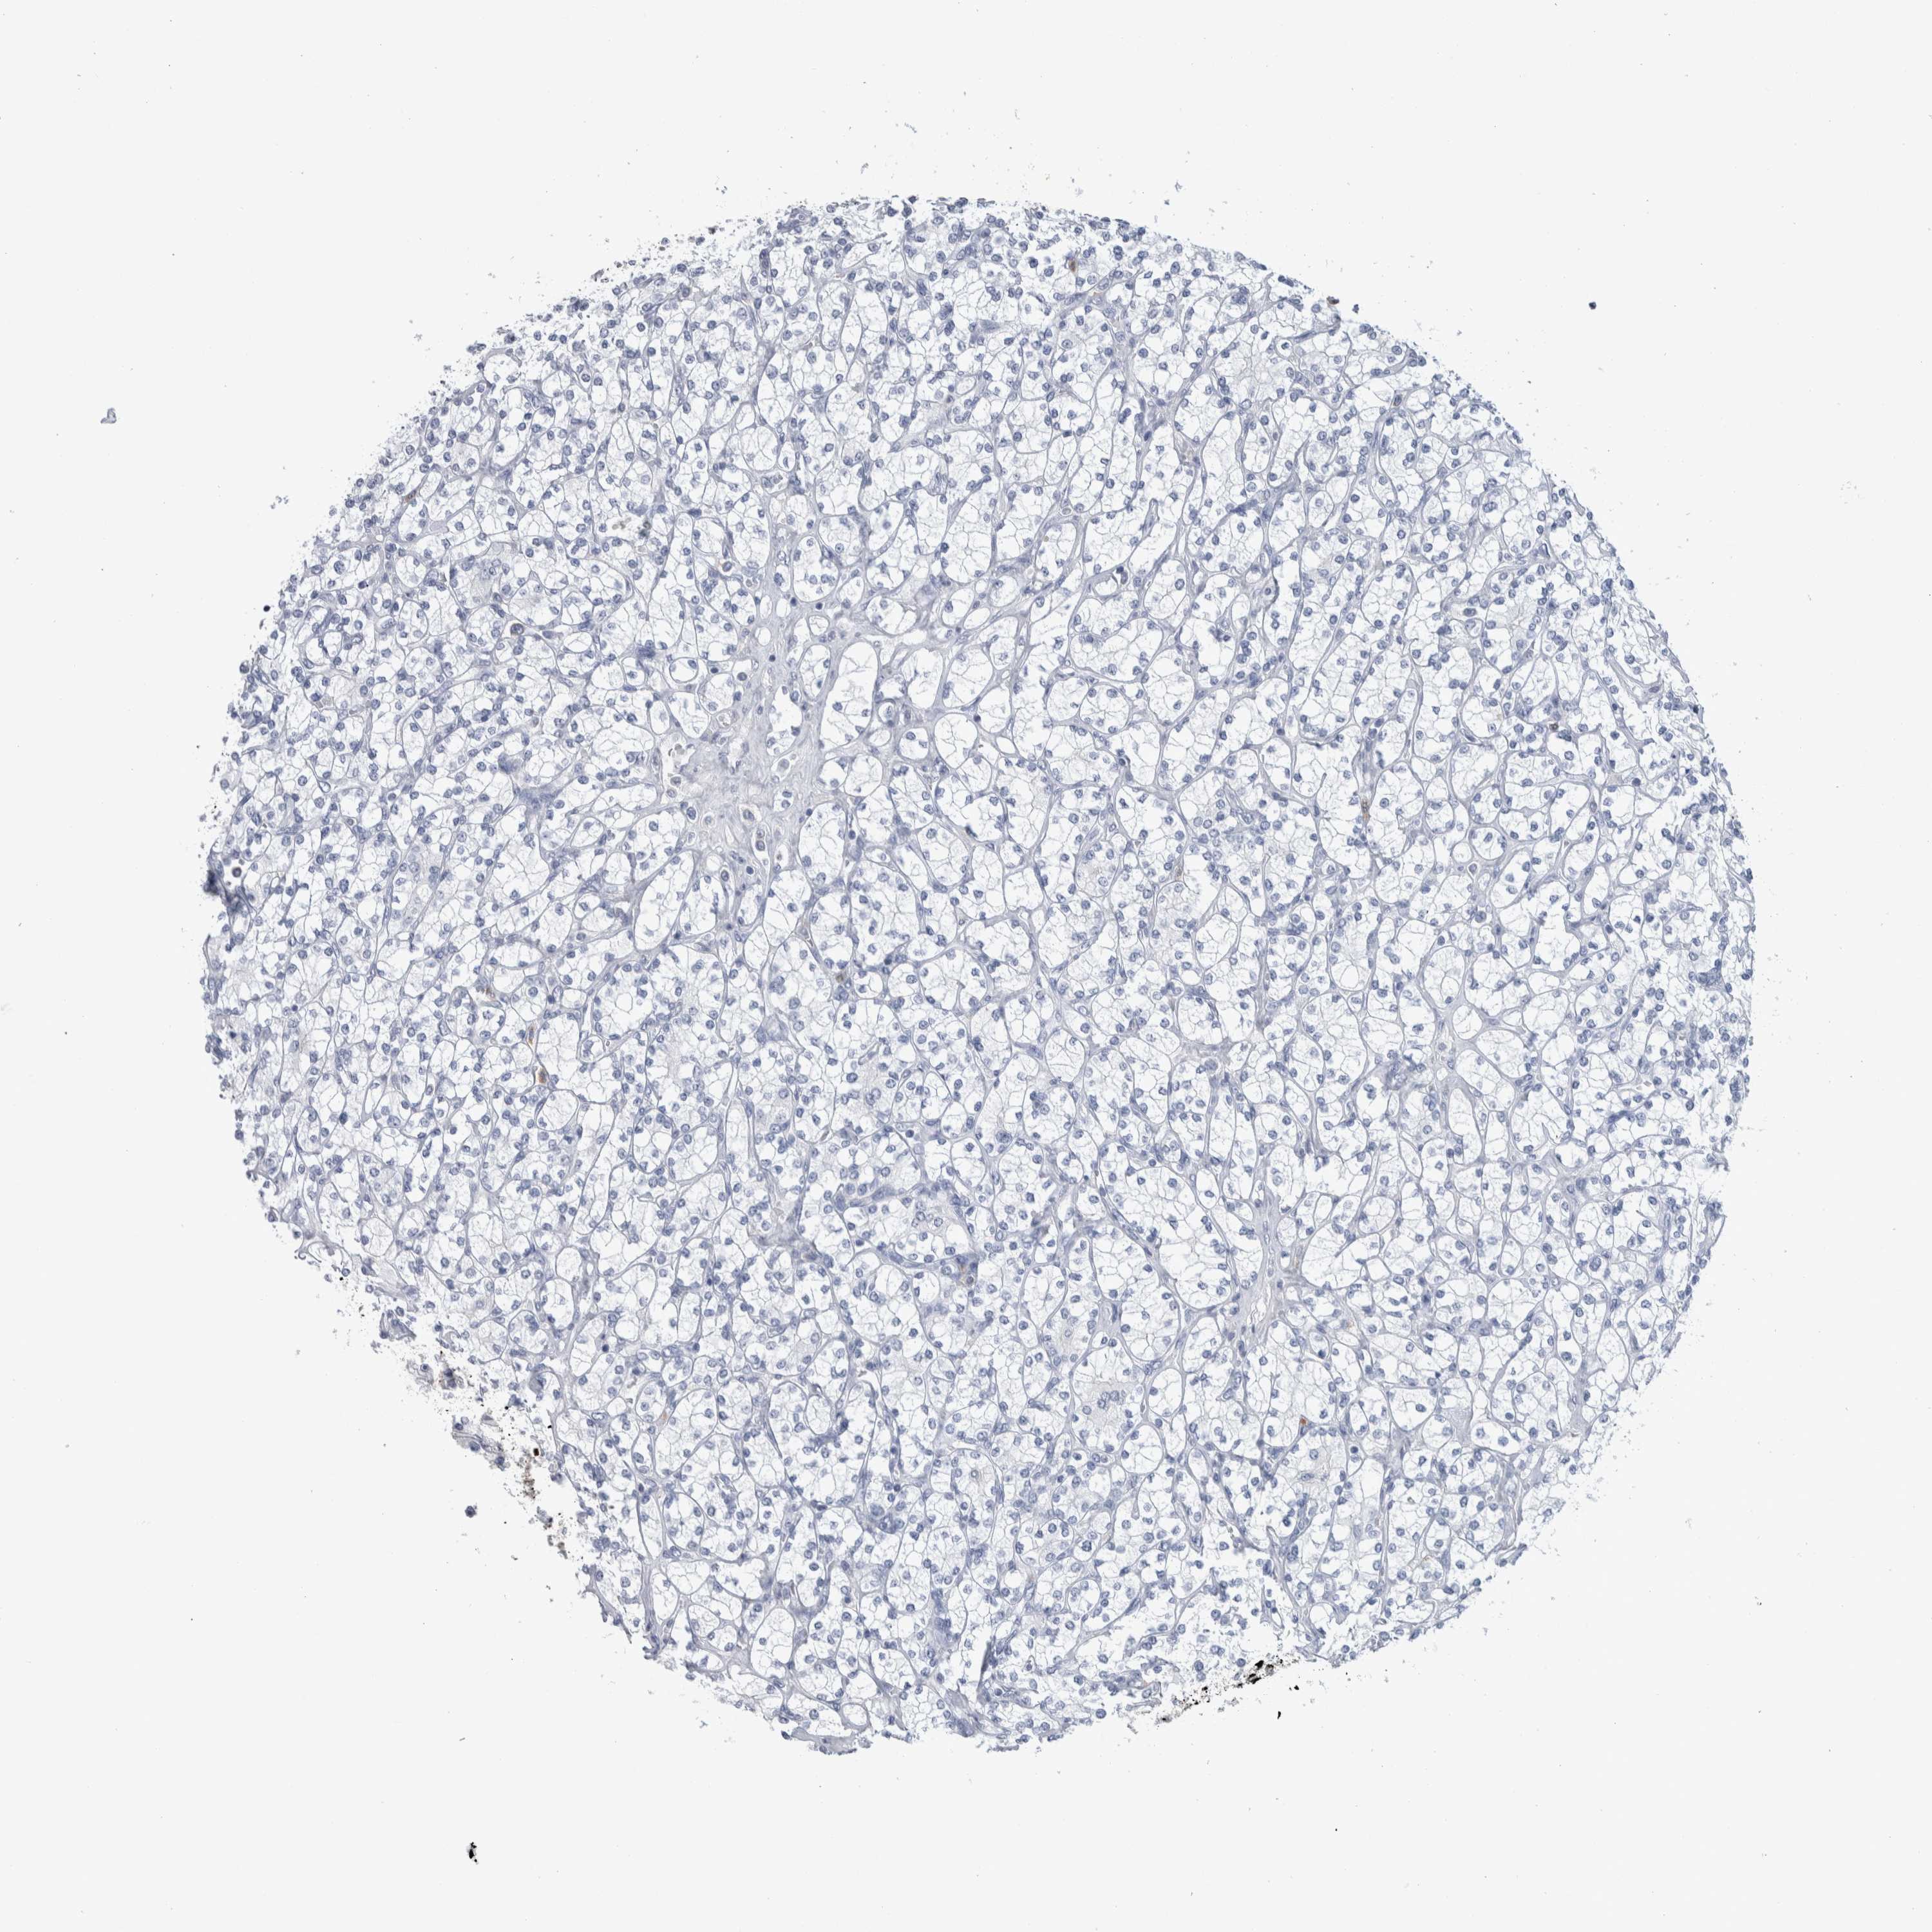

CANCER RENAL CANCER Show tissue menu

KICH TCGA KIRC TCGA KIRC VALIDATION KIRP TCGA PROTEIN RCC CPTAC PROTEIN EXPRESSION

KIDNEY CHROMOPHOBE (TCGA) - Interactive survival scatter ploti

LURAP1L is not prognostic in Kidney Chromophobe (TCGA)